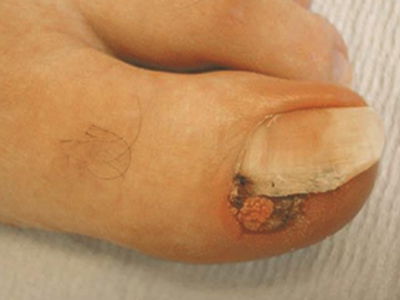

寻常疣症状图片

寻常疣可发生于身体的任何部位,但以手部为多,手外伤或水中浸泡是常见的诱发因素。典型皮损为黄豆大小或更大的灰褐色、棕色或皮色丘疹,表面粗糙,质地坚硬,可呈乳头瘤状增生。寻常疣发生在足底则为跖疣,因受压而形成淡黄或褐黄色胼胝样斑块或扁平丘疹,表面粗糙,界限清楚,边缘绕以稍高的角质环。发生在甲周者称甲周疣;发生在甲床者称甲下疣;疣体细长突起伴顶端角化者称丝状疣;发生于头皮及趾间的疣体表面常有参差不齐的突起称指状疣。